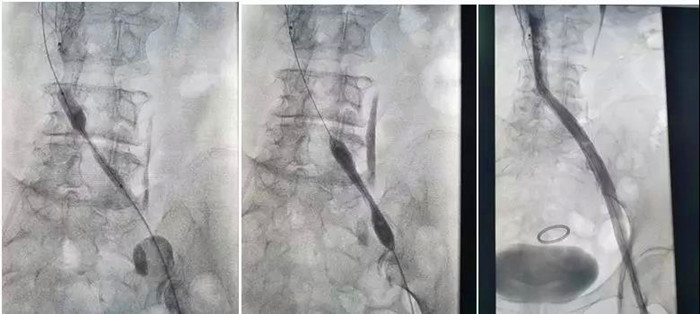

樊奶奶入住后,血管外科團(tuán)隊(duì)在陸煒的帶領(lǐng)下,爭(zhēng)分奪秒為樊奶奶研究病情,量身制定診療方案。第二天下午,陸煒為樊奶奶進(jìn)行了“下腔靜脈濾器置入+吸栓+髂靜脈支架成形術(shù)”。

明確血栓部位后,從腫脹的患肢進(jìn)入AngioJet機(jī)械血栓清除裝置,通過(guò)AngioJet吸栓導(dǎo)管?chē)娚淙芩ㄋ幬锖髮?duì)血栓進(jìn)行抽吸。血栓被一點(diǎn)一點(diǎn)抽吸干凈后,再次造影,發(fā)現(xiàn)樊奶奶果然伴有嚴(yán)重的“髂靜脈壓迫綜合征”,如果不進(jìn)行處理,血栓很容易再次復(fù)發(fā)。陸煒帶領(lǐng)血管外科手術(shù)團(tuán)隊(duì)熟練地進(jìn)行了“髂靜脈球囊擴(kuò)張和支架植入”。

溶栓、抽吸、擴(kuò)張、支架植入,手術(shù)過(guò)程扣人心弦!

一場(chǎng)手術(shù),一箭三雕,一個(gè)半小時(shí)后,樊奶奶腫脹的左腿血液運(yùn)輸終于恢復(fù)了通暢。